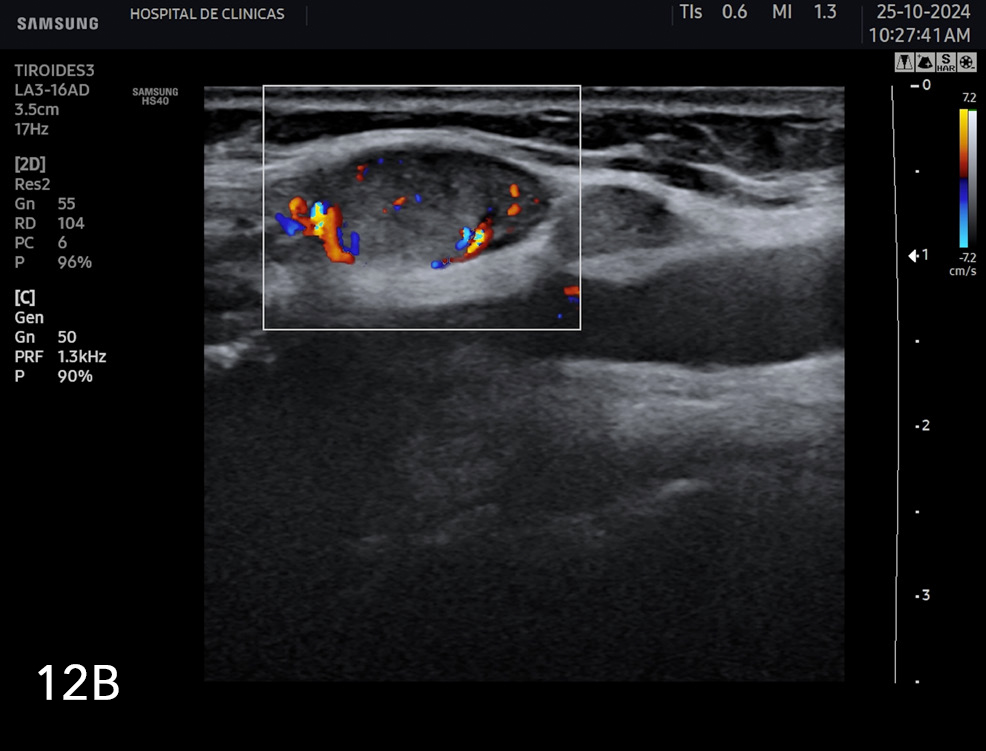

Se consideran características ultrasonográficas de adenopatías sospechosas de malignidad la quistificación, presencia de calcificaciones, pérdida de hilio graso, hiperecogenicidad, forma redondeada y vascularización anormal al Doppler. En la figura 12a y 12b se observan algunos ejemplos de adenopatías con características sospechosas de malignidad.